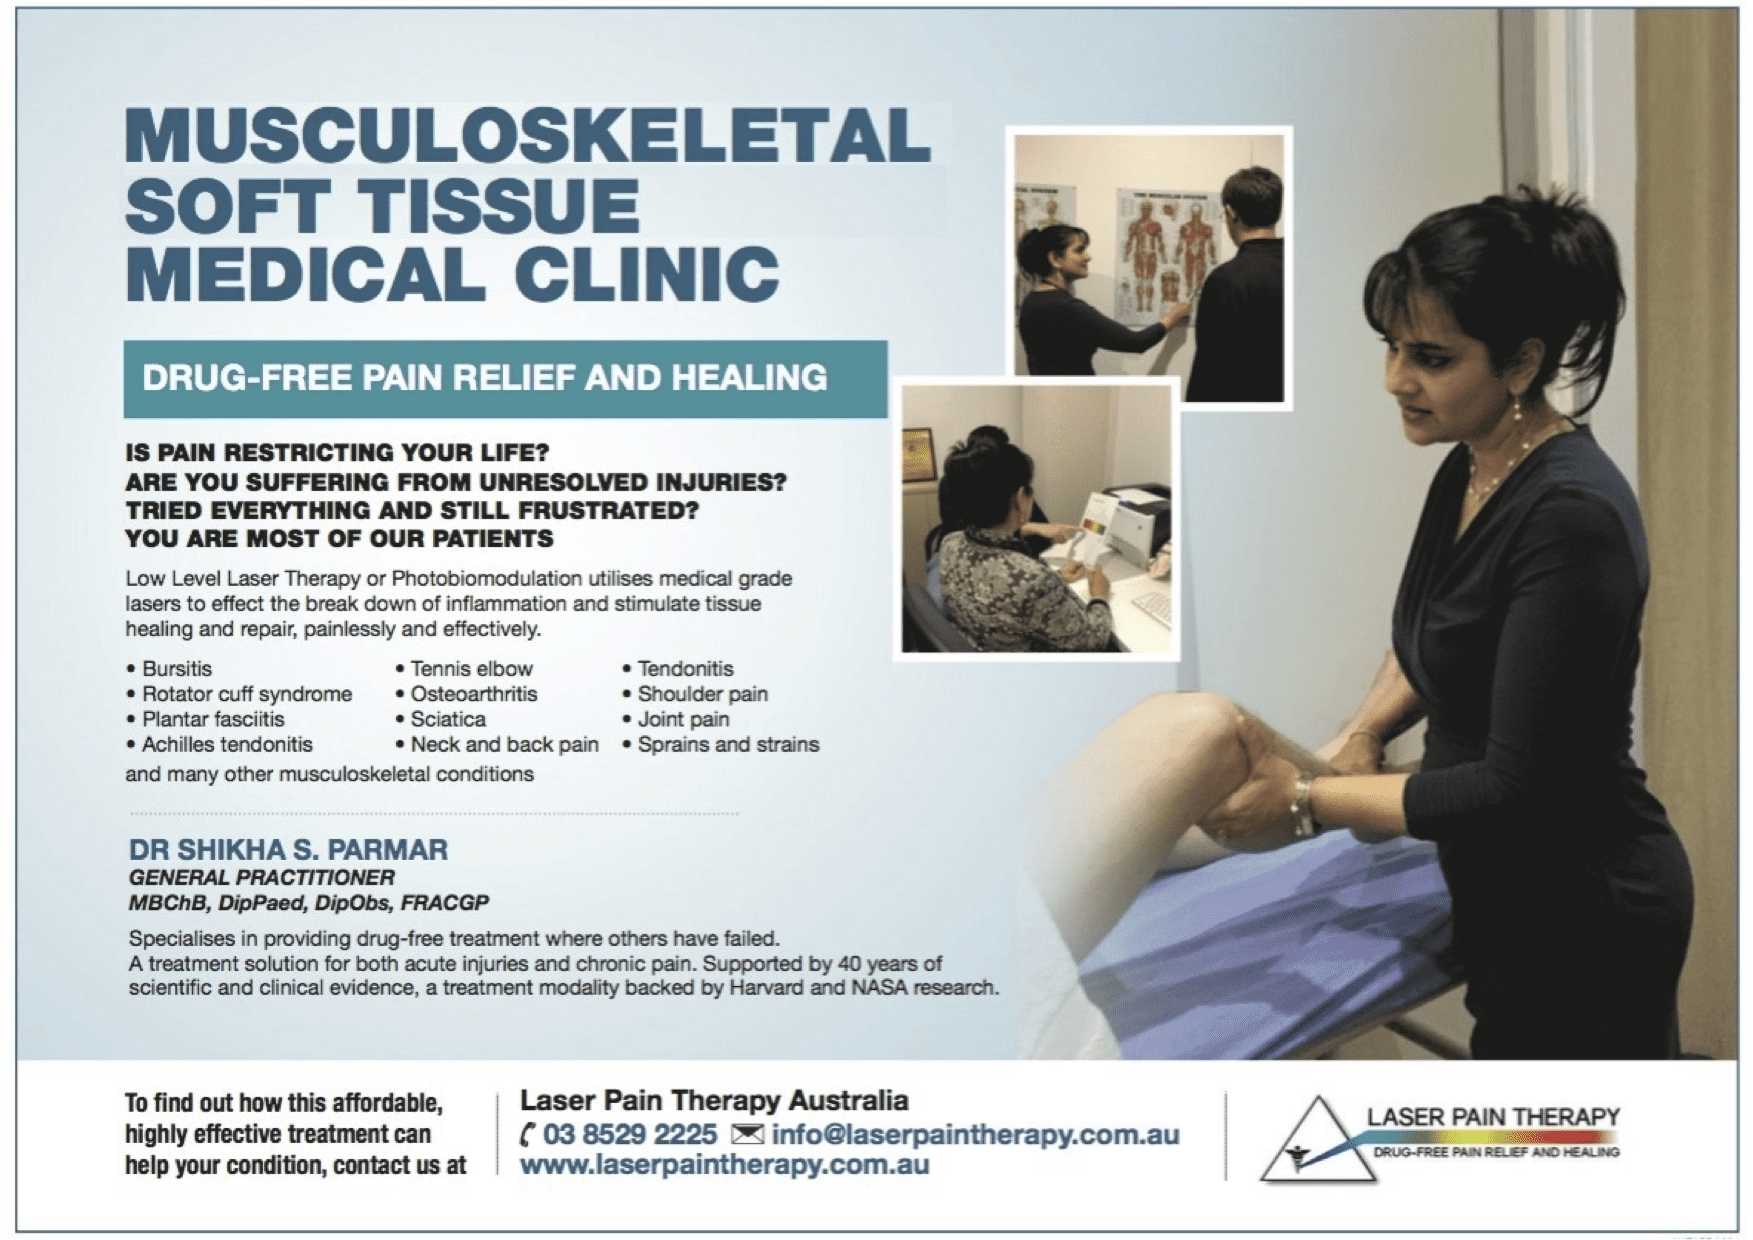

What Is Morton’s Neuroma?

Morton’s neuroma is a condition of nerve tissue damage that primarily affects the interdigital nerve (the nerve between the toes), most commonly between the third and fourth toes. It is not a true neuroma in the sense of being a growth or tumour of nerve tissue, but rather an enlargement or thickening of the nerve due to compression and irritation.

It involves:

- Enlargement of the Nerve: this results from the swelling and fibrosis of the nerve due to repeated compression or irritation. It’s often caused by the compression of the nerve between the metatarsal bones, particularly in the area where the nerve branches into the toes.

- Myelin Sheath Damage: The nerve’s myelin sheath (the protective covering around the nerve fibres) may become damaged over time due to repeated compression. This can disrupt normal nerve function, leading to pain and sensory disturbances (such as tingling or numbness).

- Inflammation of Surrounding Tissues: this may occur as a response to irritation and injury of the nerve, resulting in swelling around the affected nerve, further irritating it and making the condition more painful.

- Neuroma-like Structure Formation: over time, persistent irritation can cause a benign, non-tumour growth of nerve tissue, known as a neuroma-like structure. This is a response to nerve damage and irritation, not a true tumour, making the term “Morton’s neuroma” somewhat misleading